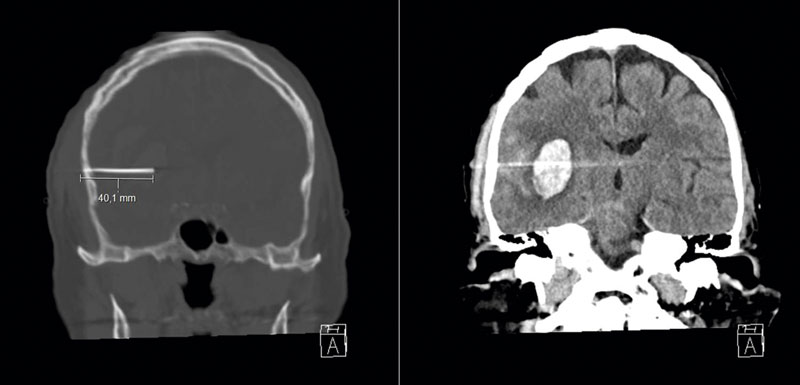

Man skjuten med en spikpistol i höger tinning. DT visade ett intracerebralt hematom. Traumamekanismen, förekomsten av blödning samt den anatomiska lokalisationen med närhet till stora kärl i fissura Sylvii motiverade utredning med DT-angiografi av huvud för att utesluta kärlskada.

Bilder från neurokirurgiska kliniken, Universitetssjukhuset i Linköping.

Äldre man med klopidogrelbehandling som råkat ut för fallolycka. Mannen var initialt vaken, men under väntan på akuten sjönk han snabbt i medvetandegrad till RLS 7 och höger pupill dilaterades. Datortomografi visar ett stort akut subduralhematom med kraftig masseffekt.

Bild från neurokirurgiska kliniken,

Universitetssjukhuset i Linköping.

2-åring som slagit i huvudet på en lekplats. Barnet blev följande timme tröttare och sjönk i medvetandegrad. Datortomografi visade ett stort epiduralhematom med anslutande fraktur, och barnet opererades akut på lokalsjukhuset med assistans av anslutande neurokirurg. Patienten skrevs ut helt återställd efter 2 dagar.